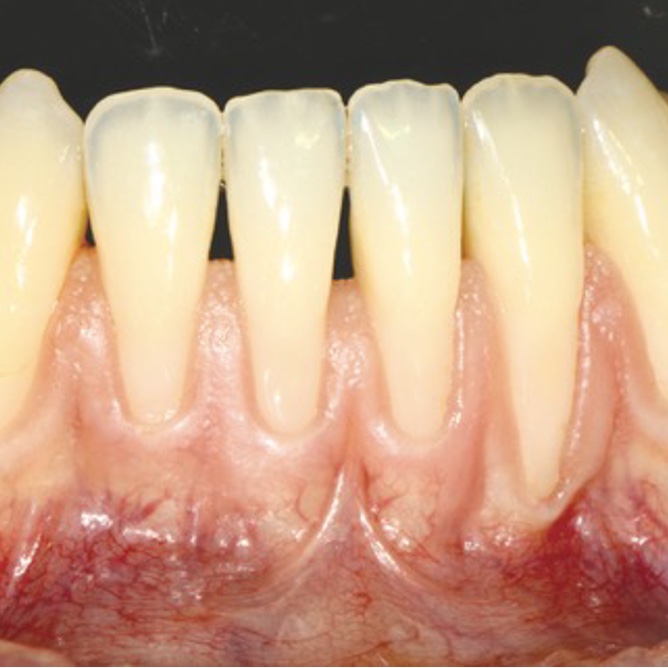

Case Report

Einsatz von Hyaluronsäure in der Behandlung von gingivalen Rezessionen Prof. Dr. Dr. Anton Sculean |